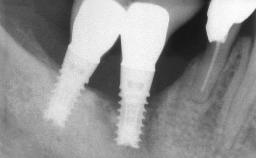

The fracture of an implant after it has been restored is one of the most severe complications. It most frequently occurs in partially edentulous jaws (1.5%). Most implant fractures involve implants with a diameter of 3.75 mm made of commercially pure titanium (Eckert 2010). Unfortunately, many cases are not reported or documented by the clinicians involved in resolving the problems created by the fracture. This case report describes the management of an implant fracture at site 36 in a middle-aged male patient. The implant had been restored with a screw-retained metal-ceramic crown.